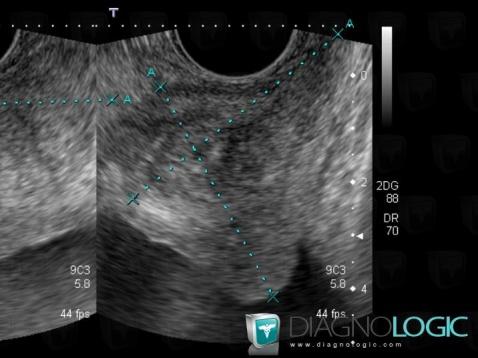

- Diagnosis Benign prostatic hyperplasia, Location(s) Prostate, with gamuts Prostatic hypertrophy